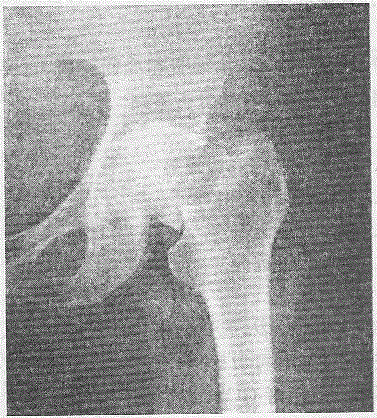

问题 女性,75岁,摔伤致左髋部疼痛、肿胀、活动受限1小时,X线检查如下图所示,断端无明显移位。 根据X线检查应诊断为

选项 A.股骨颈骨折,GardenⅠ型 B.股骨颈骨折,GardenⅡ型 C.股骨颈骨折,GardenⅢ型 D.股骨颈骨折,GardenⅣ型 E.股骨颈骨折,GardenⅤ型

答案 B